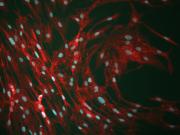

Radiothérapie : Comment les Cellules Souches Mésenchymateuses atténuent les effets secondaires

​​[Recherche à l’IRSN] En 2012, 14 millions de personnes dans le monde étaient atteintes d’un cancer, elles seront 19 millions en 2025. Dans 60 % des cas, le traitement implique des séances de radiothérapie. Cependant, les tissus sains autour de la tumeur peuvent être endommagés, pouvant entrainer des complications.

​Dans une revue parue dans l’International Journal of Molecular Sciences, le Laboratoire de radiobiologie des expositions médicales de l’IRSN met en évidence les bénéfices possibles de l’utilisation des Cellules Souches Mésenchymateuses dans le traitement de la fibrose radio-induite.